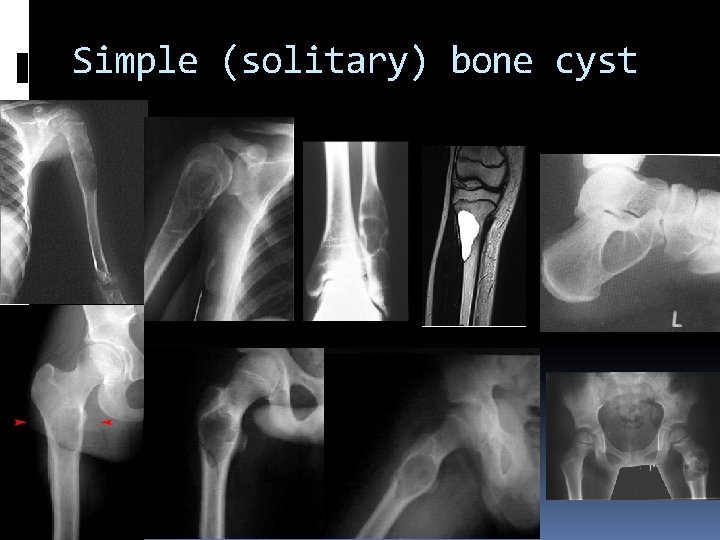

Simple (solitary) bone cyst